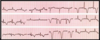

What is your interpretation?

Sinus Arrhythmia